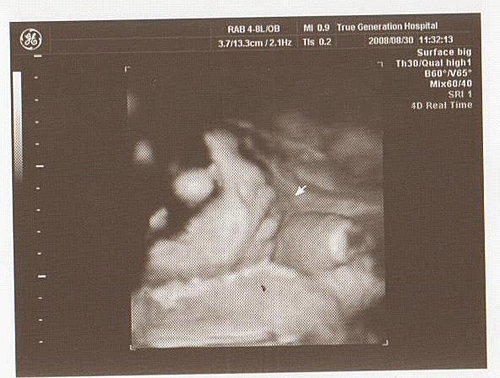

照超音波時

頭圍和腹圍都符合週數

但大腿骨大約是33週多的長度

可是侯醫師也沒有說什麼

胎兒心臟正常

胎盤也正常

沒有臍繞頸

寶寶的體重大約2455公克

預計出生時約3000~3200公克